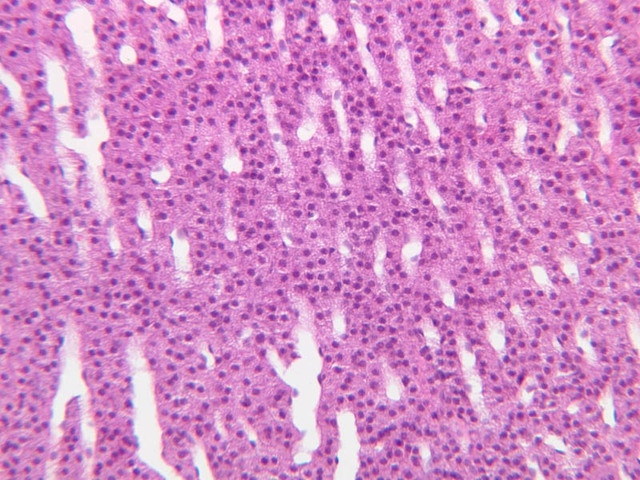

The thyroid gland (slide B-51, lead hematoxylin [10x, 20x, 40x, 40x]; B-52, H&E [10x-labeled, 20x, 40x-labeled, 40x]; B-53, PAS [2.5x, 10x, 20x, 40x]) consists of many closely packed, roughly spherical structures known as follicles, which are enclosed in a thick connective tissue capsule. Connective tissue septa extend from the capsule into the substance of the gland, carrying numerous blood vessels. Follicular cells are arranged as shells of simple cuboidal epithelium surrounding a gelatinous mass known as colloid. Look for a ring of epithelial cells around the homogeneous, pink-staining colloid. The cytoplasm of the follicular cells (principal cells) is faintly basophilic. The follicular cells secrete thyroglobulin, a glycoprotein, which is stored extracellularly in the colloid. In response to TSH, the follicular cells endocytose the colloid and hydrolyze it to form thyroxine. You can see where colloid has been resorbed because this process leaves small holes in the colloid adjacent to the follicular cells. These holes are known as resorption lacunae (B-52 [10x, 20x, 40xlabeled]). Very active follicles may exhibit a columnar epithelium and increased numbers of resorption lacunae. Between follicles, the stroma of the thyroid gland consists of a thin layer of connective tissue and a rich capillary network. Parafollicular cells (light cells or C cells) are located in the connective tissue between follicles or adjacent to follicular cells within follicles. When they lie within the follicular wall, the parafollicular cells do not reach the lumen. Parafollicular cells are slightly larger than the follicular cells and, in H & E preparations, have a more lightly stained cytoplasm (B-52, H&E [10x, 20x, 40x-labeled] [10x-labeled, 20x, 40x-labeled] [10x, 20x, 40x] [10x, 20x, 40x]; B-53, PAS [10x, 20x, 40x]). Parafollicular cells are readily identifiable in slide B-51 (stained with lead hematoxylin), where they appear as purplish-black structures in which the nuclei are difficult to discern (B-51 [10x, 20x, 40x-labeled]). These cells secrete calcitonin, which lowers serum calcium levels by inhibiting bone resorption and accelerating osteoid calcification.